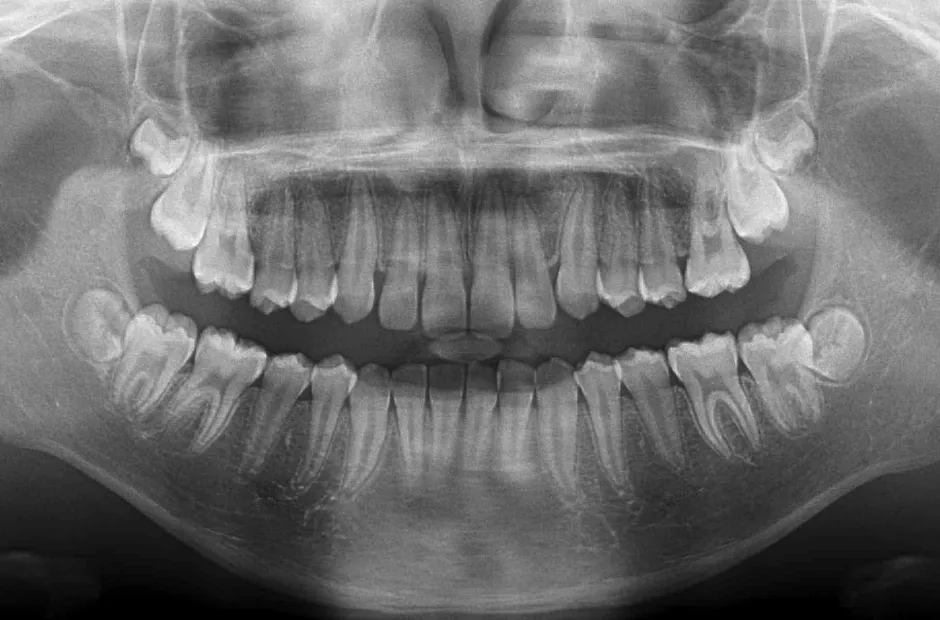

出っ歯

| 診断名・主訴 | 出っ歯 |

|---|---|

| 年齢・性別 | 16歳・男性 |

| 治療期間・回数 | 1年4か月 |

| 治療に用いた主な装置 | ブラケット |

| 抜歯部位 | 上顎4,4 |

| 治療費 | 60万円(税抜) |

| リスク・副作用 | 装置による違和感・疼痛・歯肉退縮・歯根吸収・虫歯のリスクなど |

治療前

治療後